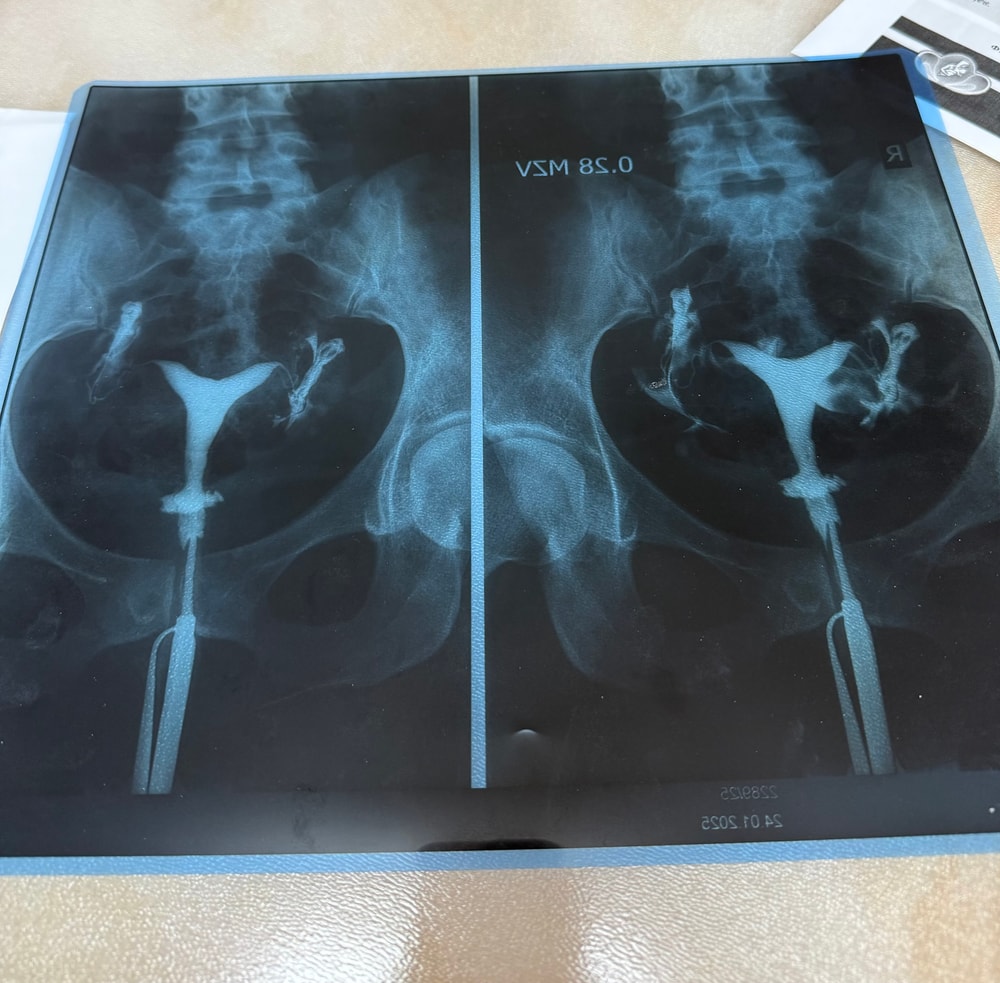

Анастасия Головина, Да, снимок и описание гсг есть, прикрепляю Вам, гормоны сдавала месяцев 5-6 назад, всё было в норме. Изображение Изображение

У вас двурогая матка, не полная перегородка, по УЗИ овуляция была верный признак наличие свободной жидкости в позади маточном пространстве